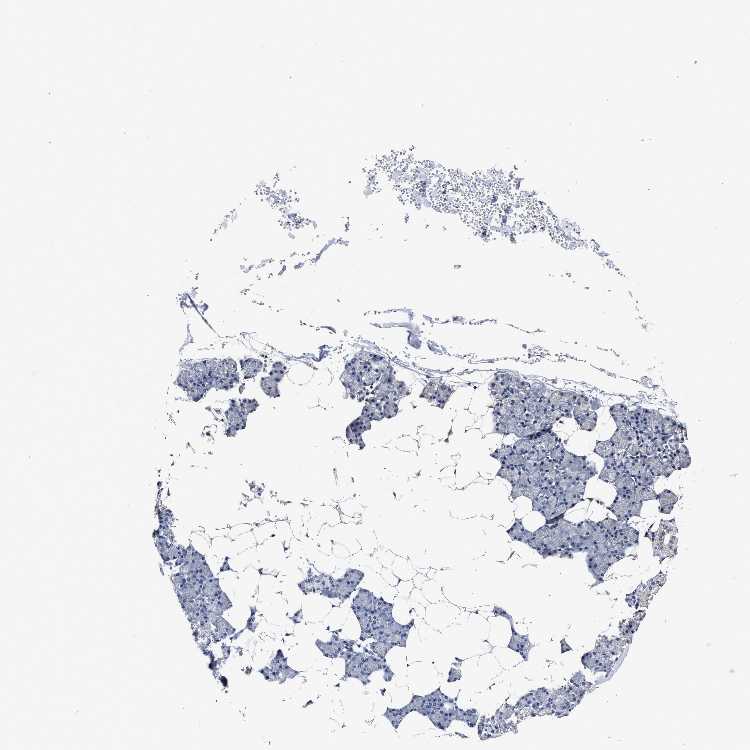

SALIVARY GLAND - Antibody stainingi

Antibody staining in the annotated cell types in the current human tissue is reported as not detected, low, medium, or high, based on conventional immunohistochemistry profiling in selected tissues. This score is based on the combination of the staining intensity and fraction of stained cells.

Each image is clickable and will lead to virtual microscopy that enables deeper exploration of all samples and also displays staining intensity scores, fraction scores and subcellular localization as well as patient and tissue information for each sample.

Antibody HPA020884Antibody CAB025510

Glandular cells Not detectedMedium